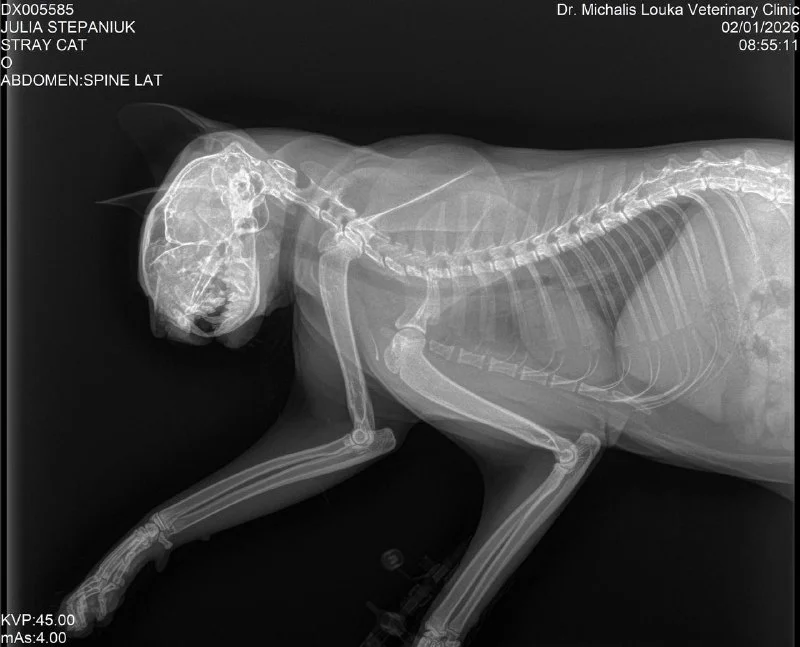

Right now CAR HIT this cat front of me.😧

Итак, новости. Сегодня заехала к котику. Его прооперировали, буквально собирали челюсть. Таз тоже переломан, но там операция не нужна. Сейчас стоит трубка в шее до желудка, чтобы кормить.

Получила предварительный счет на сегодня 😵💫

Умоляю, помогите оплатить 🙏

Revolut: +35799 377 950 (nadzeyjhpd)

К этому же номеру quick pay Bank of Cyprus

PayPal: [email protected]